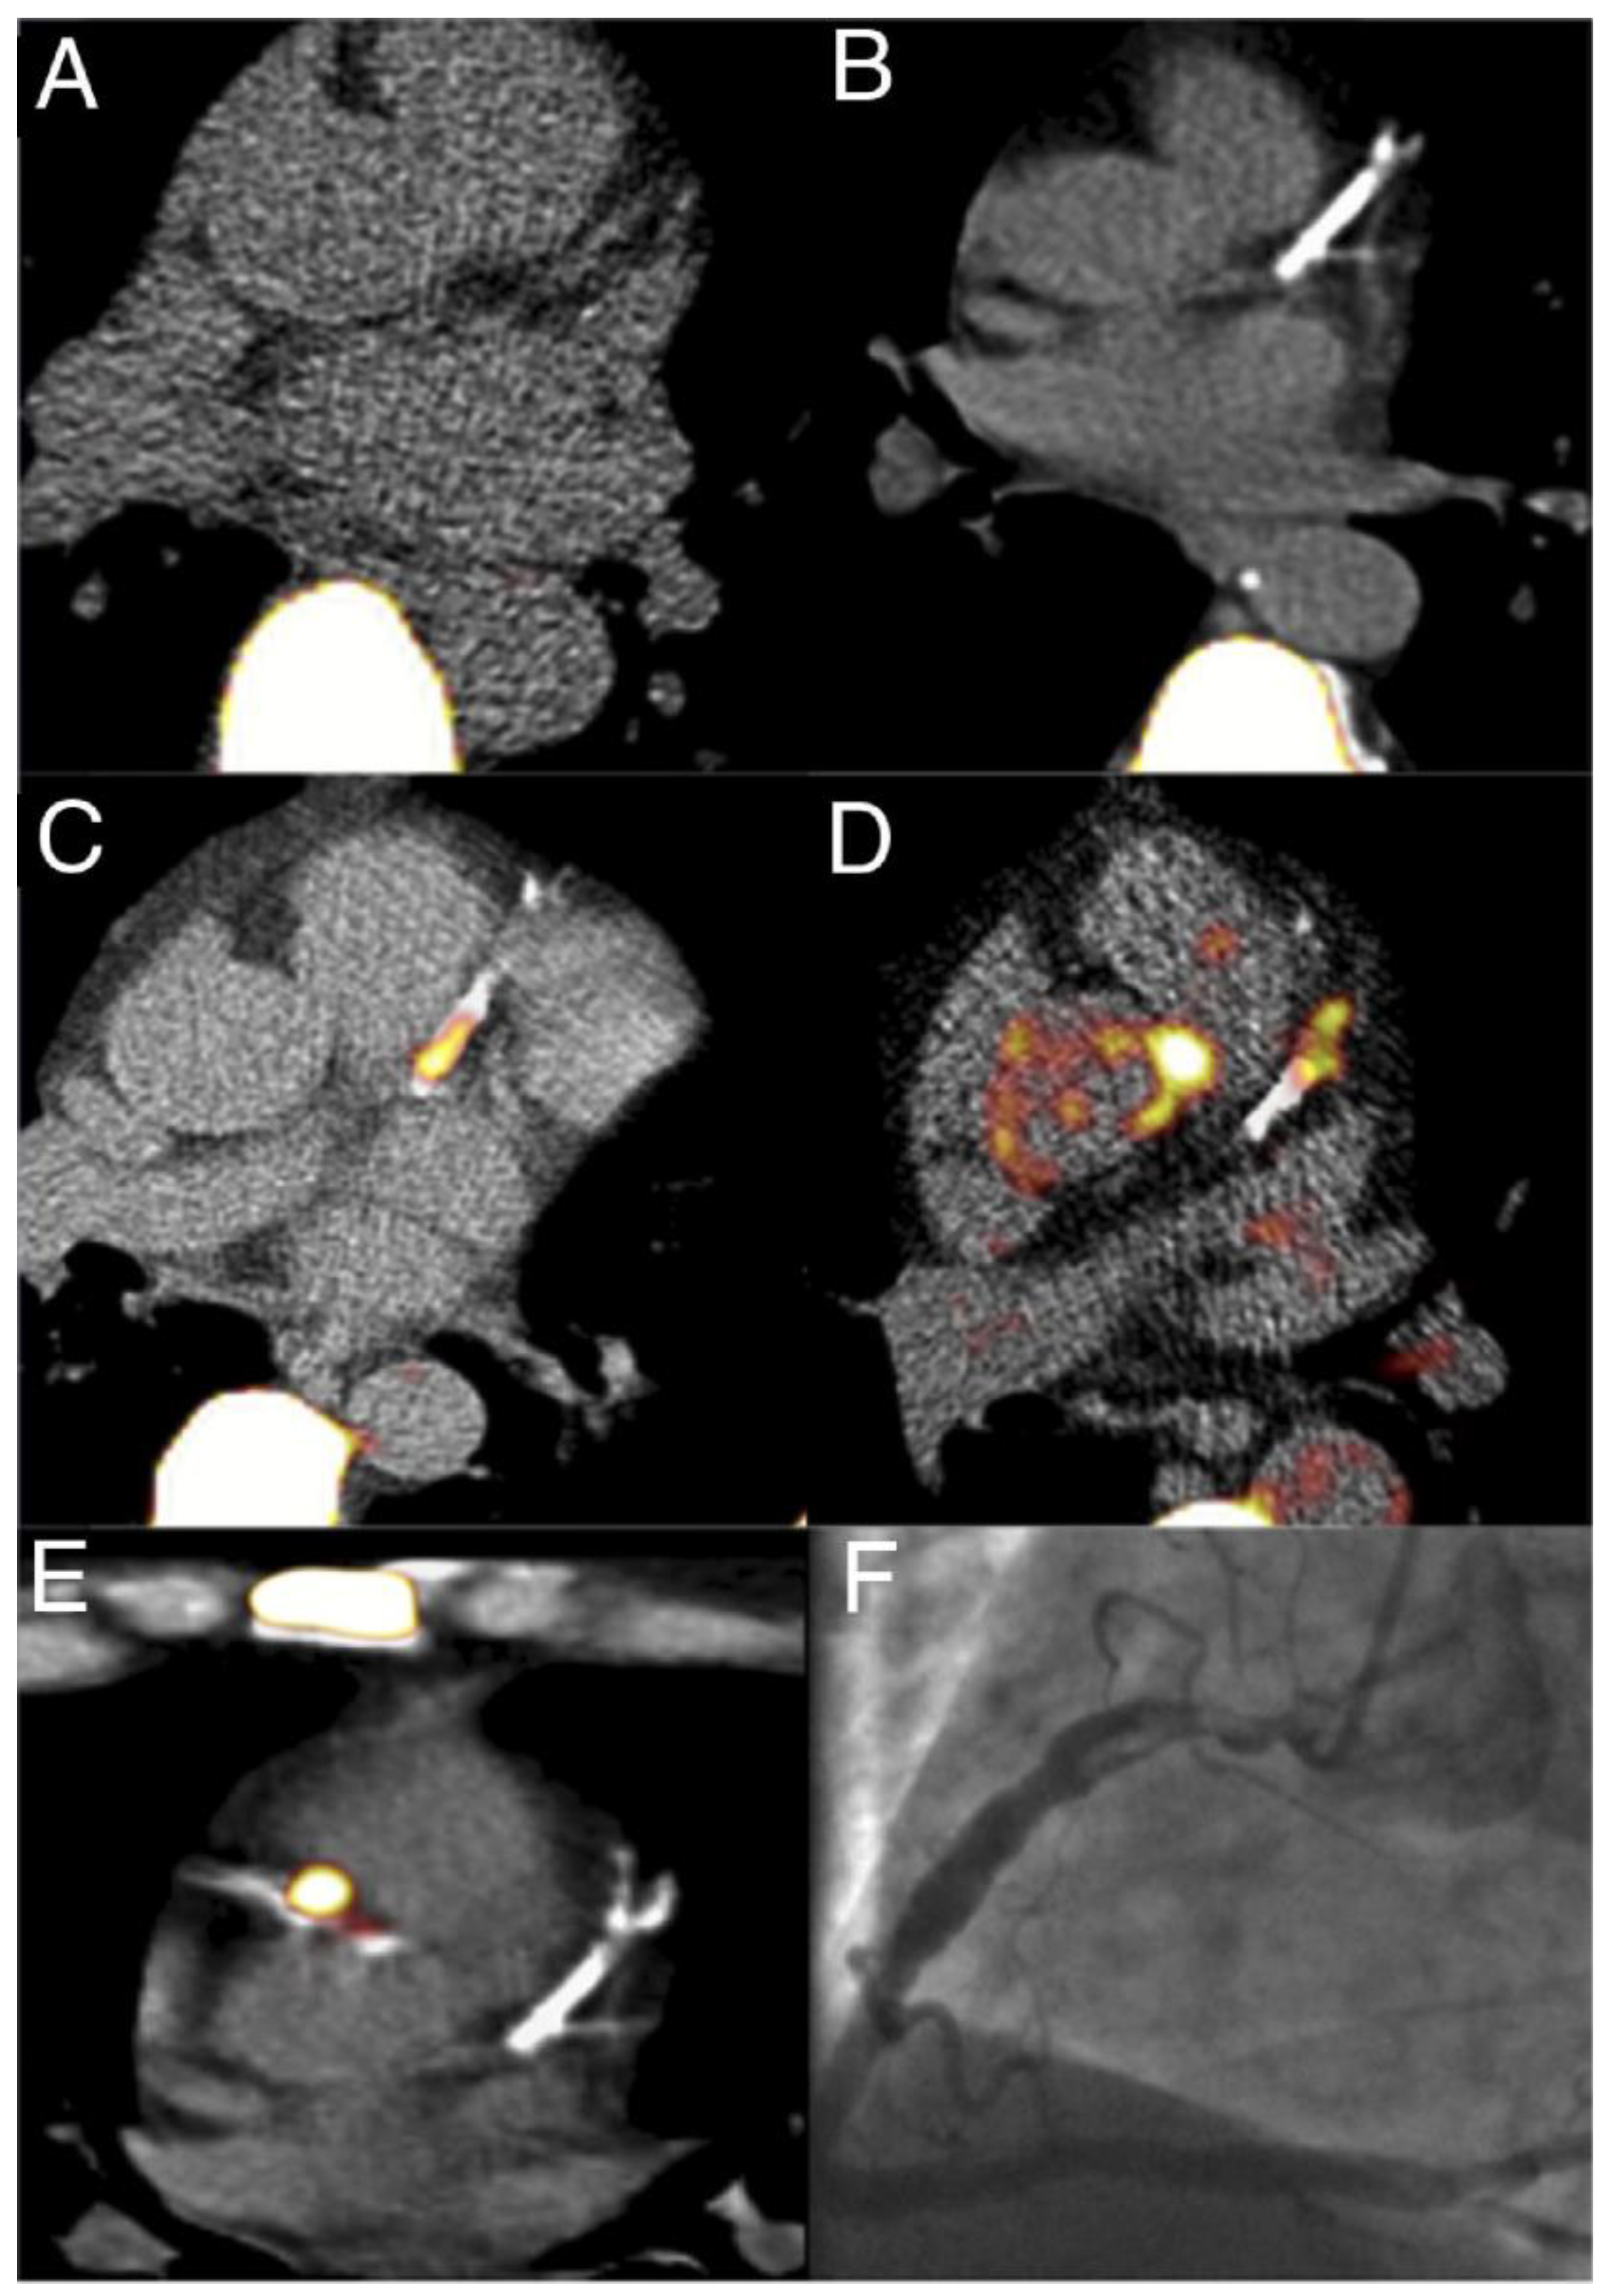

- Joshi, N.V.; Vesey, A.T.; Williams, M.C.; Shah, A.S.V.; A Calvert, P.; Craighead, F.H.M.; Yeoh, S.E.; Wallace, W.; Salter, D.; Fletcher, A.M.; et al. 18F-fluoride positron emission tomography for identification of ruptured and high-risk coronary atherosclerotic plaques: A prospective clinical trial. Lancet 2014, 383, 705–713. [Google Scholar] [CrossRef]

- Lee, J.M.; Bang, J.-I.; Koo, B.-K.; Hwang, D.; Park, J.; Zhang, J.; Yaliang, T.; Suh, M.; Paeng, J.C.; Shiono, Y.; et al. Clinical Relevance of 18 F-Sodium Fluoride Positron-Emission Tomography in Noninvasive Identification of High-Risk Plaque in Patients With Coronary Artery Disease. Circ. Cardiovasc. Imaging. 2017, 10. [Google Scholar] [CrossRef]

- Early detection of vulnerable coronary plaques because 18F NaF accumulation in micro-calcification before visibility on CT, allowing earlier intervention. Furthermore, 18F NaF uptake can differentiate between active and indolent calcification in coronary arteries, providing crucial information on plaque activity and potential instability.

- Dweck, M.R.; Chow, M.W.; Joshi, N.V.; Williams, M.C.; Jones, C.; Fletcher, A.M.; Richardson, H.; White, A.; McKillop, G.; van Beek, E.J.; et al. Coronary arterial 18F-sodium fluoride uptake: A novel marker of plaque biology. J. Am. Coll. Cardiol. 2012, 59, 1539–1548. [Google Scholar] [CrossRef]